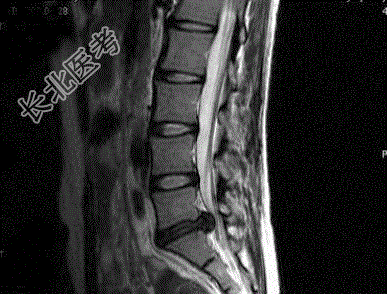

- 单项选择题女,37岁, 腰腿痛半年,结合图像, 最可能的诊断是

A、L

-S

椎间盘变性B、L

椎间盘向后突出C、L

椎间盘变性并向后突出D、L

椎间盘膨出E、L4~5椎间盘向后突出